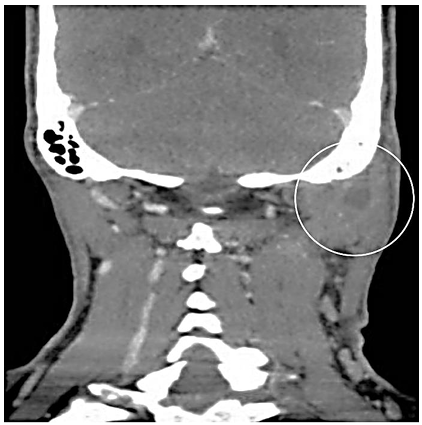

Homem, 46 anos, com quadro de otorreia, otalgia, febre e edema cervical ipsilateral às queixas otológicas, é submetido à tomografia computadorizada de mastoides com contraste (imagem abaixo):

Acerca do caso em questão, o diagnóstico mais provável e a conduta mais adequada é: